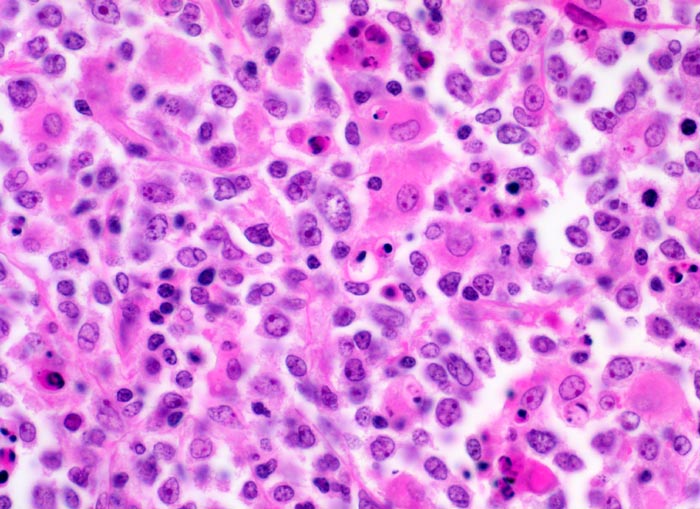

Diffuses grosszelliges B-Zell Lymphom

Lymphknoten, abdominal

Mittelgrosse polymorphe Tumorzellen mit unregelmässig geformten, teils lobulierten Kernen. Gelegentlich sind mehrere randständige Nukleolen erkennbar (Zentroblastische Variante). Schmaler Zytoplasmasaum. Neben den Tumorzellen sind zahlreiche Histiozyten mit reichlich eosinophilem Zytoplasma und ovalen Kernen ohne Atypien nachweisbar. Das Zytoplasma der Histiozyten enthält teilweise phagozytierte Zelltrümmer.

Magenlymphom mit Befall abdominaler Lymphknoten.

400